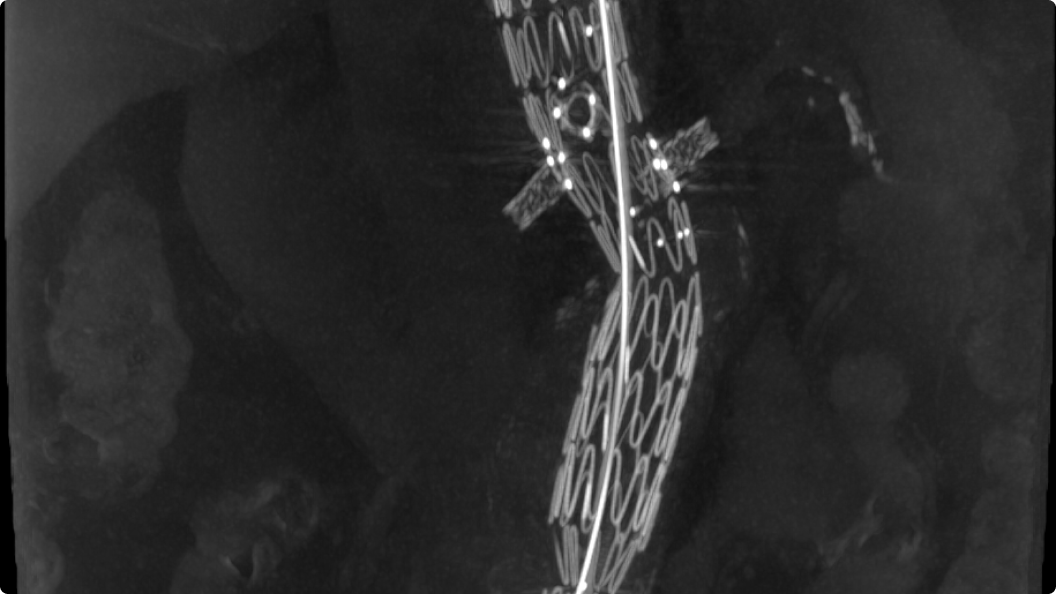

MAR11

Reduzierung von Metallartefakten, Optimierung der Bildqualität

MAR11 (Metallic Artifact Reduction, Metallartefaktreduktion) ist eine fortschrittliche Technologie zur Reduzierung von Artefakten, die durch Metallgegenstände im Körper, zum Beispiel Implantate, verursacht werden. Diese Artefakte können wichtige anatomische Details verdecken. Dies erschwert es dem Klinikteam, Diagnosen zu stellen und Behandlungen genau zu planen.

MAR11 gewährleistet eine verbesserte Bildqualität und ist demnach ein wertvolles Instrument zur Verbesserung der Genauigkeit und Sicherheit minimalinvasiver Verfahren.

feature-4